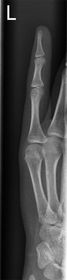

| What's the evaluation criteria for the PA Finger X-Ray? | ANATOMY: distal phalynx -> distal 1/2 of metacarpal demonstrated CRITERIA: - equal concavity on both sides of phalanges - IP and MCP open - no overlapping of adjacent fingers POSITIONING: CR perpendicular @ PIP joint |

| What's the evaluation criteria for the Lateral finger x-ray? | ANATOMY: entire digit demonstrated CRITERIA: open joint spaces concave to one side, while the dorsal side is straight no overlapping of adjacent fingers/soft tissues POSITIONING: CR perpendicular @ PIP joint |

| Oblique finger x-ray image criteria? | ANATOMY: entire digit demonstrated CRITERIA: more concavity to one side open joint spaces no superimposition of adjacent fingers POSITIONING: CR perpendicular @ PIP joint |